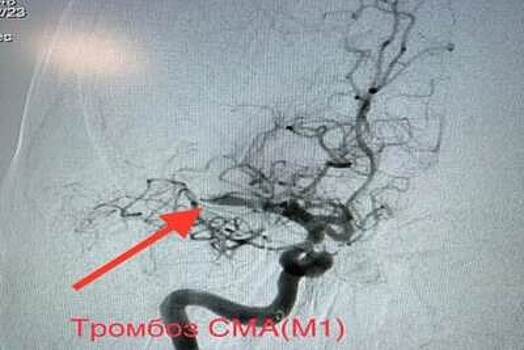

Медики из сосудистого центра Воскресенской больницы спасли 54-летнюю пациентку, у которой был диагностирован обширный инсульт, сообщает пресс-служба министерства здравоохранения Московской области. Женщину доставила в больницу скорая медицинская помощь. Пациентка жаловалась на головокружение, слабость и онемение в левой руке и ноге. Обследование показало, что у нее острый тромбоз средней мозговой артерии и критическое сужение правой внутренней и наружной сонной артерии. Медики предупреждают, что если в данном случае не предпринять меры, то это может привести к инвалидности, нарушению двигательной активности, речи и другим последствиям. «Нами было принято решение о проведении экстренной операции. Пациентке выполнили тромбоэкстракцию, то есть удалили тромб из средней мозговой артерии через небольшой прокол в ноге. После этого было проведено стентирование внутренней сонной артерии справа. Операция проведена эндоваскулярно с помощью ангиографической установки», - отметил заведующий сосудистым центром Воскресенской больницы Гурген Айвазян. Специалист подчеркнул, что плюсом этой методики проведения операции является то, что вмешательство проводится без разрезов и наркоза. Операция прошла успешно. Сейчас женщина чувствует себя хорошо и продолжает лечение в стационаре.